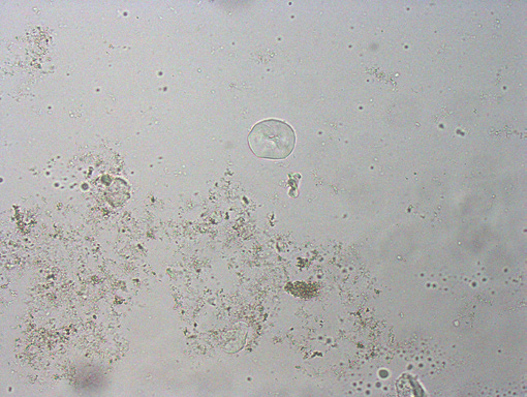

图29 (a)鸟粪石晶体。背景为许多无定形的磷酸盐晶体。较大晶体具有典型的鸟粪石三维结构。USG 1.056,pH值8.5。瑞氏染色细胞学检查发现球菌。(b)鸟粪石晶体。背景中有许多无定形的磷酸盐晶体和球菌。(c)注意该图右侧有两个星星状的晶体团块。图片来自Dr. Heather L. Wamsley, Bradenton, FL。